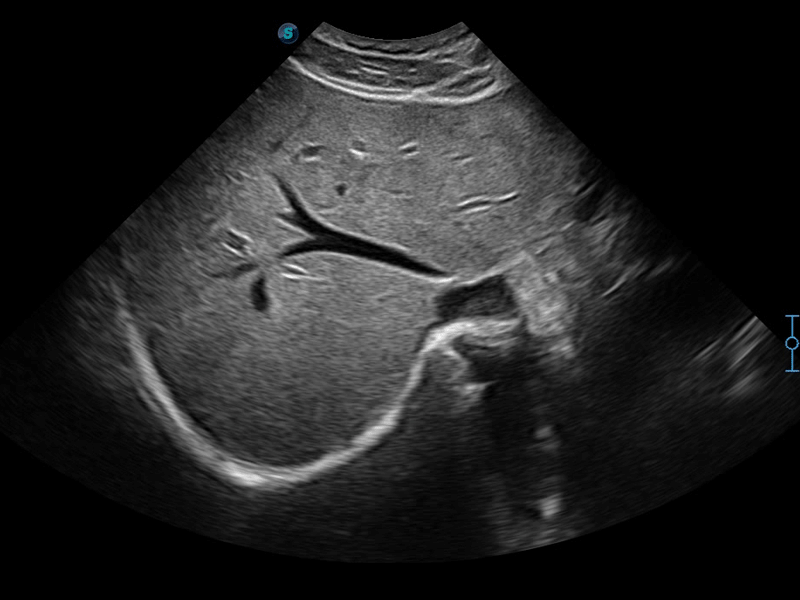

实时宽景成像技术

通过彩色血流和实时宽景相结合,可观察到完整的动静脉血流,方便医生检查。实时扫查过程中,如有任何操作失误也可以很容易地进行回扫擦除,而不会中断扫查。

临床图像